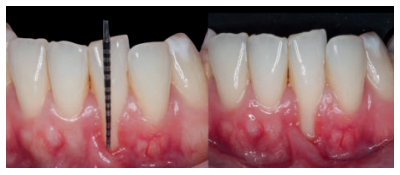

Previamente a la intervención, la paciente se enjuagó durante 1 minuto con un colutorio de clorhexidina. La técnica quirúrgica comenzó con la preparación del lecho receptor, para ello se realizó una incisión sulcular a espesor parcial a nivel de la recesión, se continúo diseccionando apical y lateralmente, extendiéndose de 3 a 5 mm de la recesión para permitir la entrada del ITC y su estabilización. Posteriormente, se realizó una incisión en el fondo de vestíbulo, dejando un puente de tejido que servirá para un doble aporte sanguíneo al injerto (Figura 2).

Una vez creado el lecho receptor, se procedió a la obtención de un ITC de la mucosa masticatoria palatina y a la sutura de dicho injerto mediante dos puntos colchoneros horizontales, uno situado en la parte mesial y otro en la parte distal del sobre. Para mayor adaptación y estabilización de las papilas se realizó un punto suspensorio cogiendo papila e ITC, mediante sutura de 6/0 no reabsorbible (Figura 3).